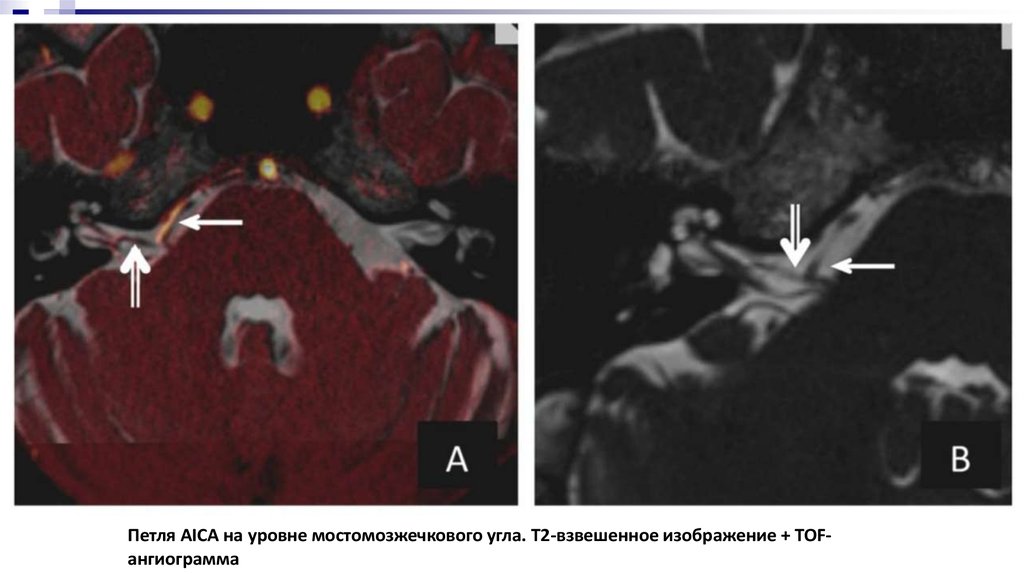

Петля AICA на уровне мостомозжечкового угла. Т2-взвешенное изображение + TOFангиограмма